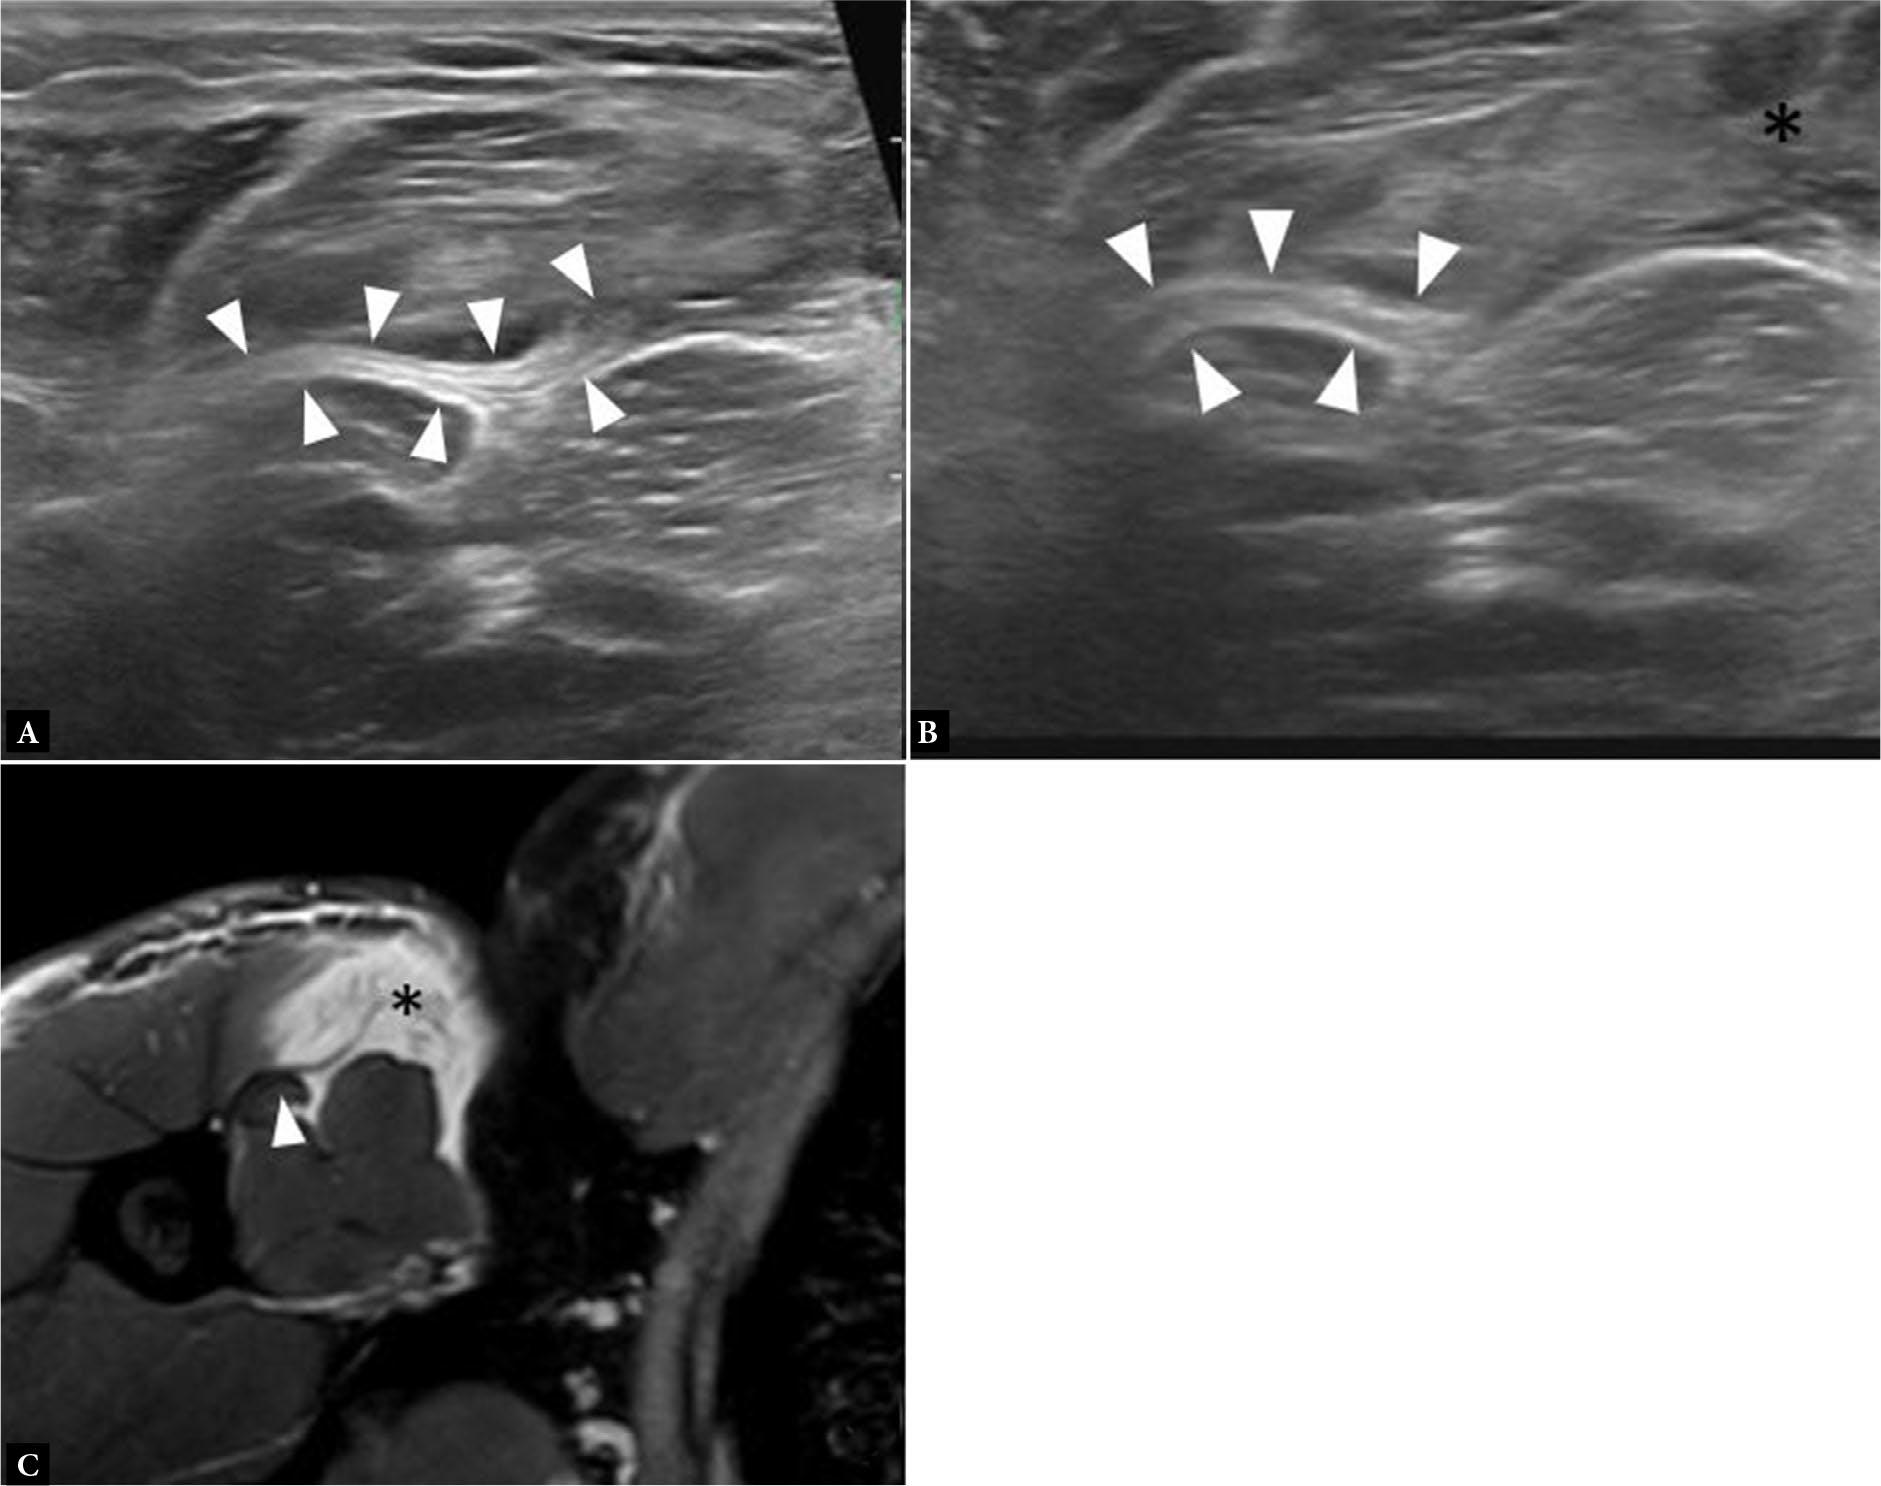

Fig. 3.

Axial T1-weighted MR image (A) and long axis gray scale ultrasound image (B) of the arm show the relationship between the PM tendon (solid arrowheads) and the regional anatomy: long head biceps brachii tendon (arrow), short head biceps brachii muscle (asterisk), and coracobrachialis muscle (open arrowhead)

MRI affords superior contrast resolution between the intermediate signal of muscle, hypointense signal of tendon, and the fluid signal hyperintensity that is associated with injury. The pathologic fluid signal is best depicted on fat saturated (FS) T2-weighted (T2-w) sequences, which are complemented by the anatomical detail better visualized on T1-weighted (T1-w) sequences. While sequence selection varies between institutions, most protocols typically contain axial, coronal, and sagittal fluid-sensitive sequences, such as T2-w FS, proton density (PD) FS, or short tau inversion recovery (STIR), as well as axial T1-w and coronal T1-w or PD sequences. Axial images are particularly useful in identifying the relationship between the PM tendon, biceps brachii and coracobrachialis muscle (Fig. 3). Occasionally, the axial images will be a smaller field of view to facilitate injury detection at the distal tendon insertion. Sagittal and coronal imaging planes help further characterize the extent and location of PM injury. This can include additional coronal oblique imaging in the plane of the PM muscle and tendon. Standard imaging time is approximately 45 minutes.

US provides a portable, more cost-effective, and faster alternative to MRI and affords superior spatial resolution. Although US is more user-dependent, studies have shown inter-observer reliability in detecting PM injury and adequate correlation with MRI and intraoperative findings(8,12). US assessment is conducted with a linear high-resolution transducer positioned transverse and longitudinal to the longitudinal axis of the PM muscle. The muscular clavicular and sternal segments are imaged from their origins to the common tendon insertion onto the humerus. Care is taken to identify the relationship of the PM tendon with respect to the regional anatomy. This includes following the bicipital groove in the transverse plane inferiorly to locate the PM tendon, which crosses superficial to the long head biceps brachii tendon and inserts on the lateral margin of the groove (Fig. 3). In addition, the short head biceps brachii muscle has been described as a useful anatomical landmark and can be followed from the coracoid process of the scapula inferiorly, superficial to which the PM tendon and myotendinous junction course.